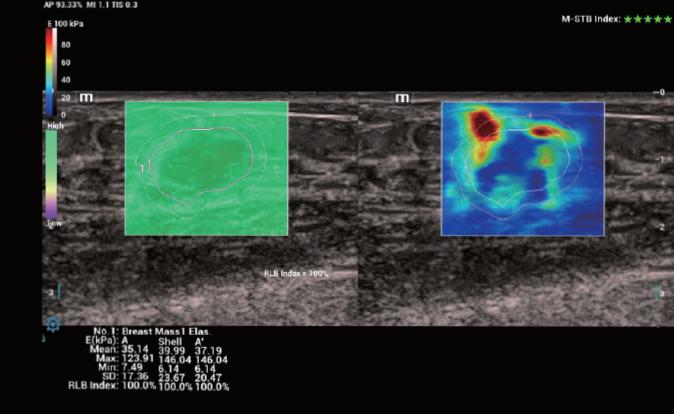

Strain Elastography Оценка эластичности ткани методом компрессионной эластографии (с программой анализа)

STE Оценка эластичности ткани методом эластографии сдвиговой волны (метод 2D-с формированием двухмерной цветовой эластограммы и количественной оценкой эластичности)

STQ Оценка эластичности ткани методом эластографии сдвиговой волны (количественная оценка эластичности в зоне интереса)

SmartBreast Протокол определения и анализа образований молочной железы по системе TI-RADS